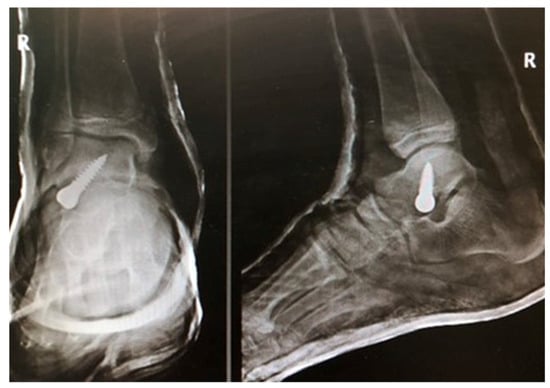

Arthroereisis with a Talar Screw in Symptomatic Flexible Flatfoot in Children

Bobiński, A.; Tomczyk, Ł.; Pelc, M.; Chruścicki, D.A.; Śnietka, B.; Morasiewicz, P. Arthroereisis with a Talar Screw in Symptomatic Flexible Flatfoot in Children. J. Clin. Med. 2023, 12, 7475. https://doi.org/10.3390/jcm12237475